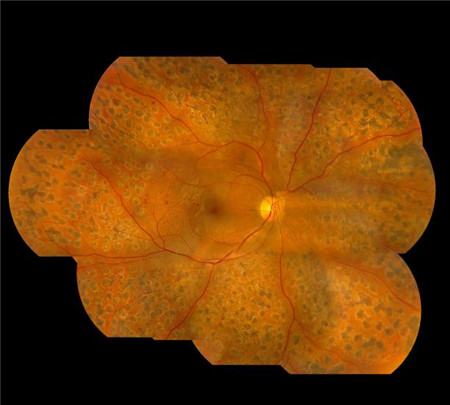

要知道,長期的異常血糖狀態會破壞視網膜上的微絲血管,引起視網膜微絲血管病變,而發生視網膜脫落、黃斑水腫以及玻璃體出血這三種形式的視網膜病變。

那么,面對可怕的糖尿病視網膜病變,糖尿病患者應該怎么辦呢?希瑪眼科建議,每個糖尿病患者除了需要控制好血糖,還應做到:不管視力是否下降,每年都應該至少做一次眼底檢查,爭取能夠早發現、早治療。